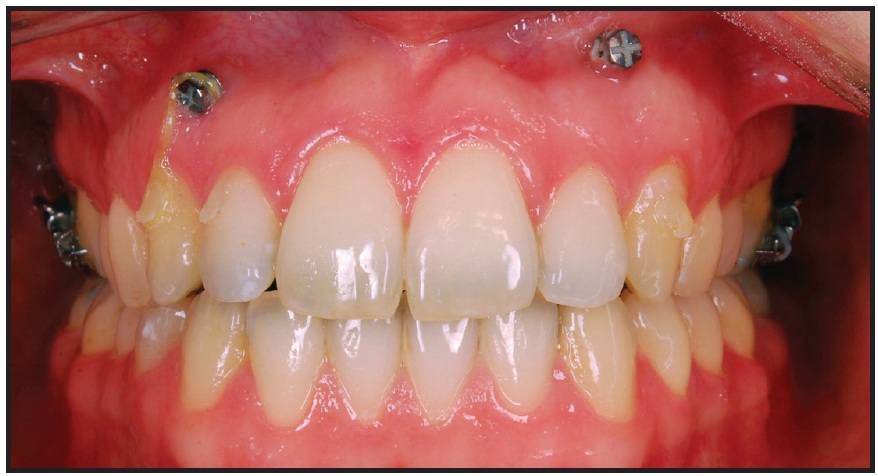

Two Dual-Top* JA standard mini-implants (1.6mm x 10mm) were placed distal to the second molars in the maxillary tuberosities (Fig. 2). One and a half months later, since the patient wanted to be treated with invisible appliances, the Incognito** lingual system was bonded and an .014" nickel titanium archwire was inserted (Fig. 3). This appliance is compatible with skeletal anchorage and has proven reliable in complex treatments. Gentle force was applied with elastic chain from the miniscrews to distalize the upper teeth. To prevent undesirable transverse movement of the molars, tubes or brackets were bonded to the buccal surfaces of the first and second molars and connected by sectional .016" x .022" nickel titanium wires.

Fig. 2 Six months after extraction of upper third molars, one Dual-Top* mini-implant placed in each maxillary tuberosity.

Fig. 3 One and a half months later, Incognito** lingual bracket system bonded, .014" nickel titanium archwire inserted, and gentle forces applied with power chain from miniscrews to distalize upper teeth. Tubes or brackets bonded to buccal surfaces of first and second molars and sectional .016" × .022" nickel titanium wires placed to prevent undesirable transverse movement.